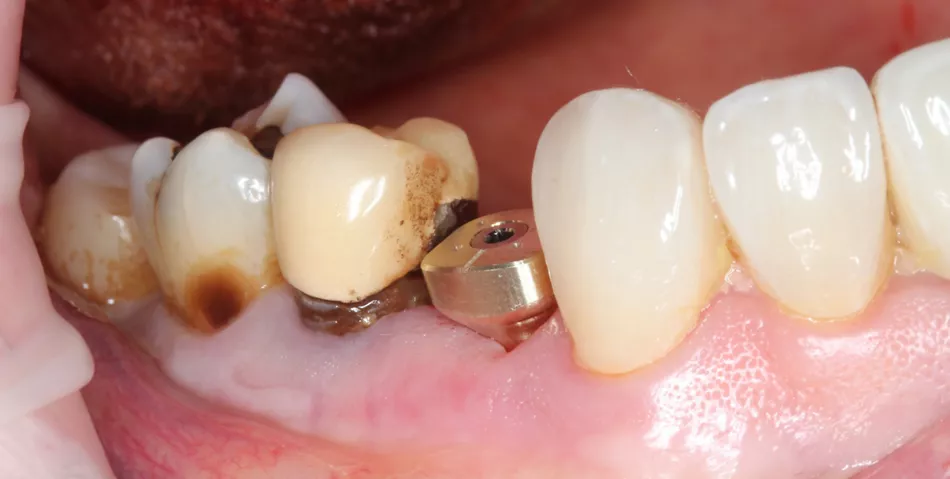

Initial situation

1. Panoramic view showing severe bone loss around tooth 15, confirming hopeless prognosis.

1

2a. 2b. Preoperative frontal and occlusal view of the lower arch showing multiple missing teeth.